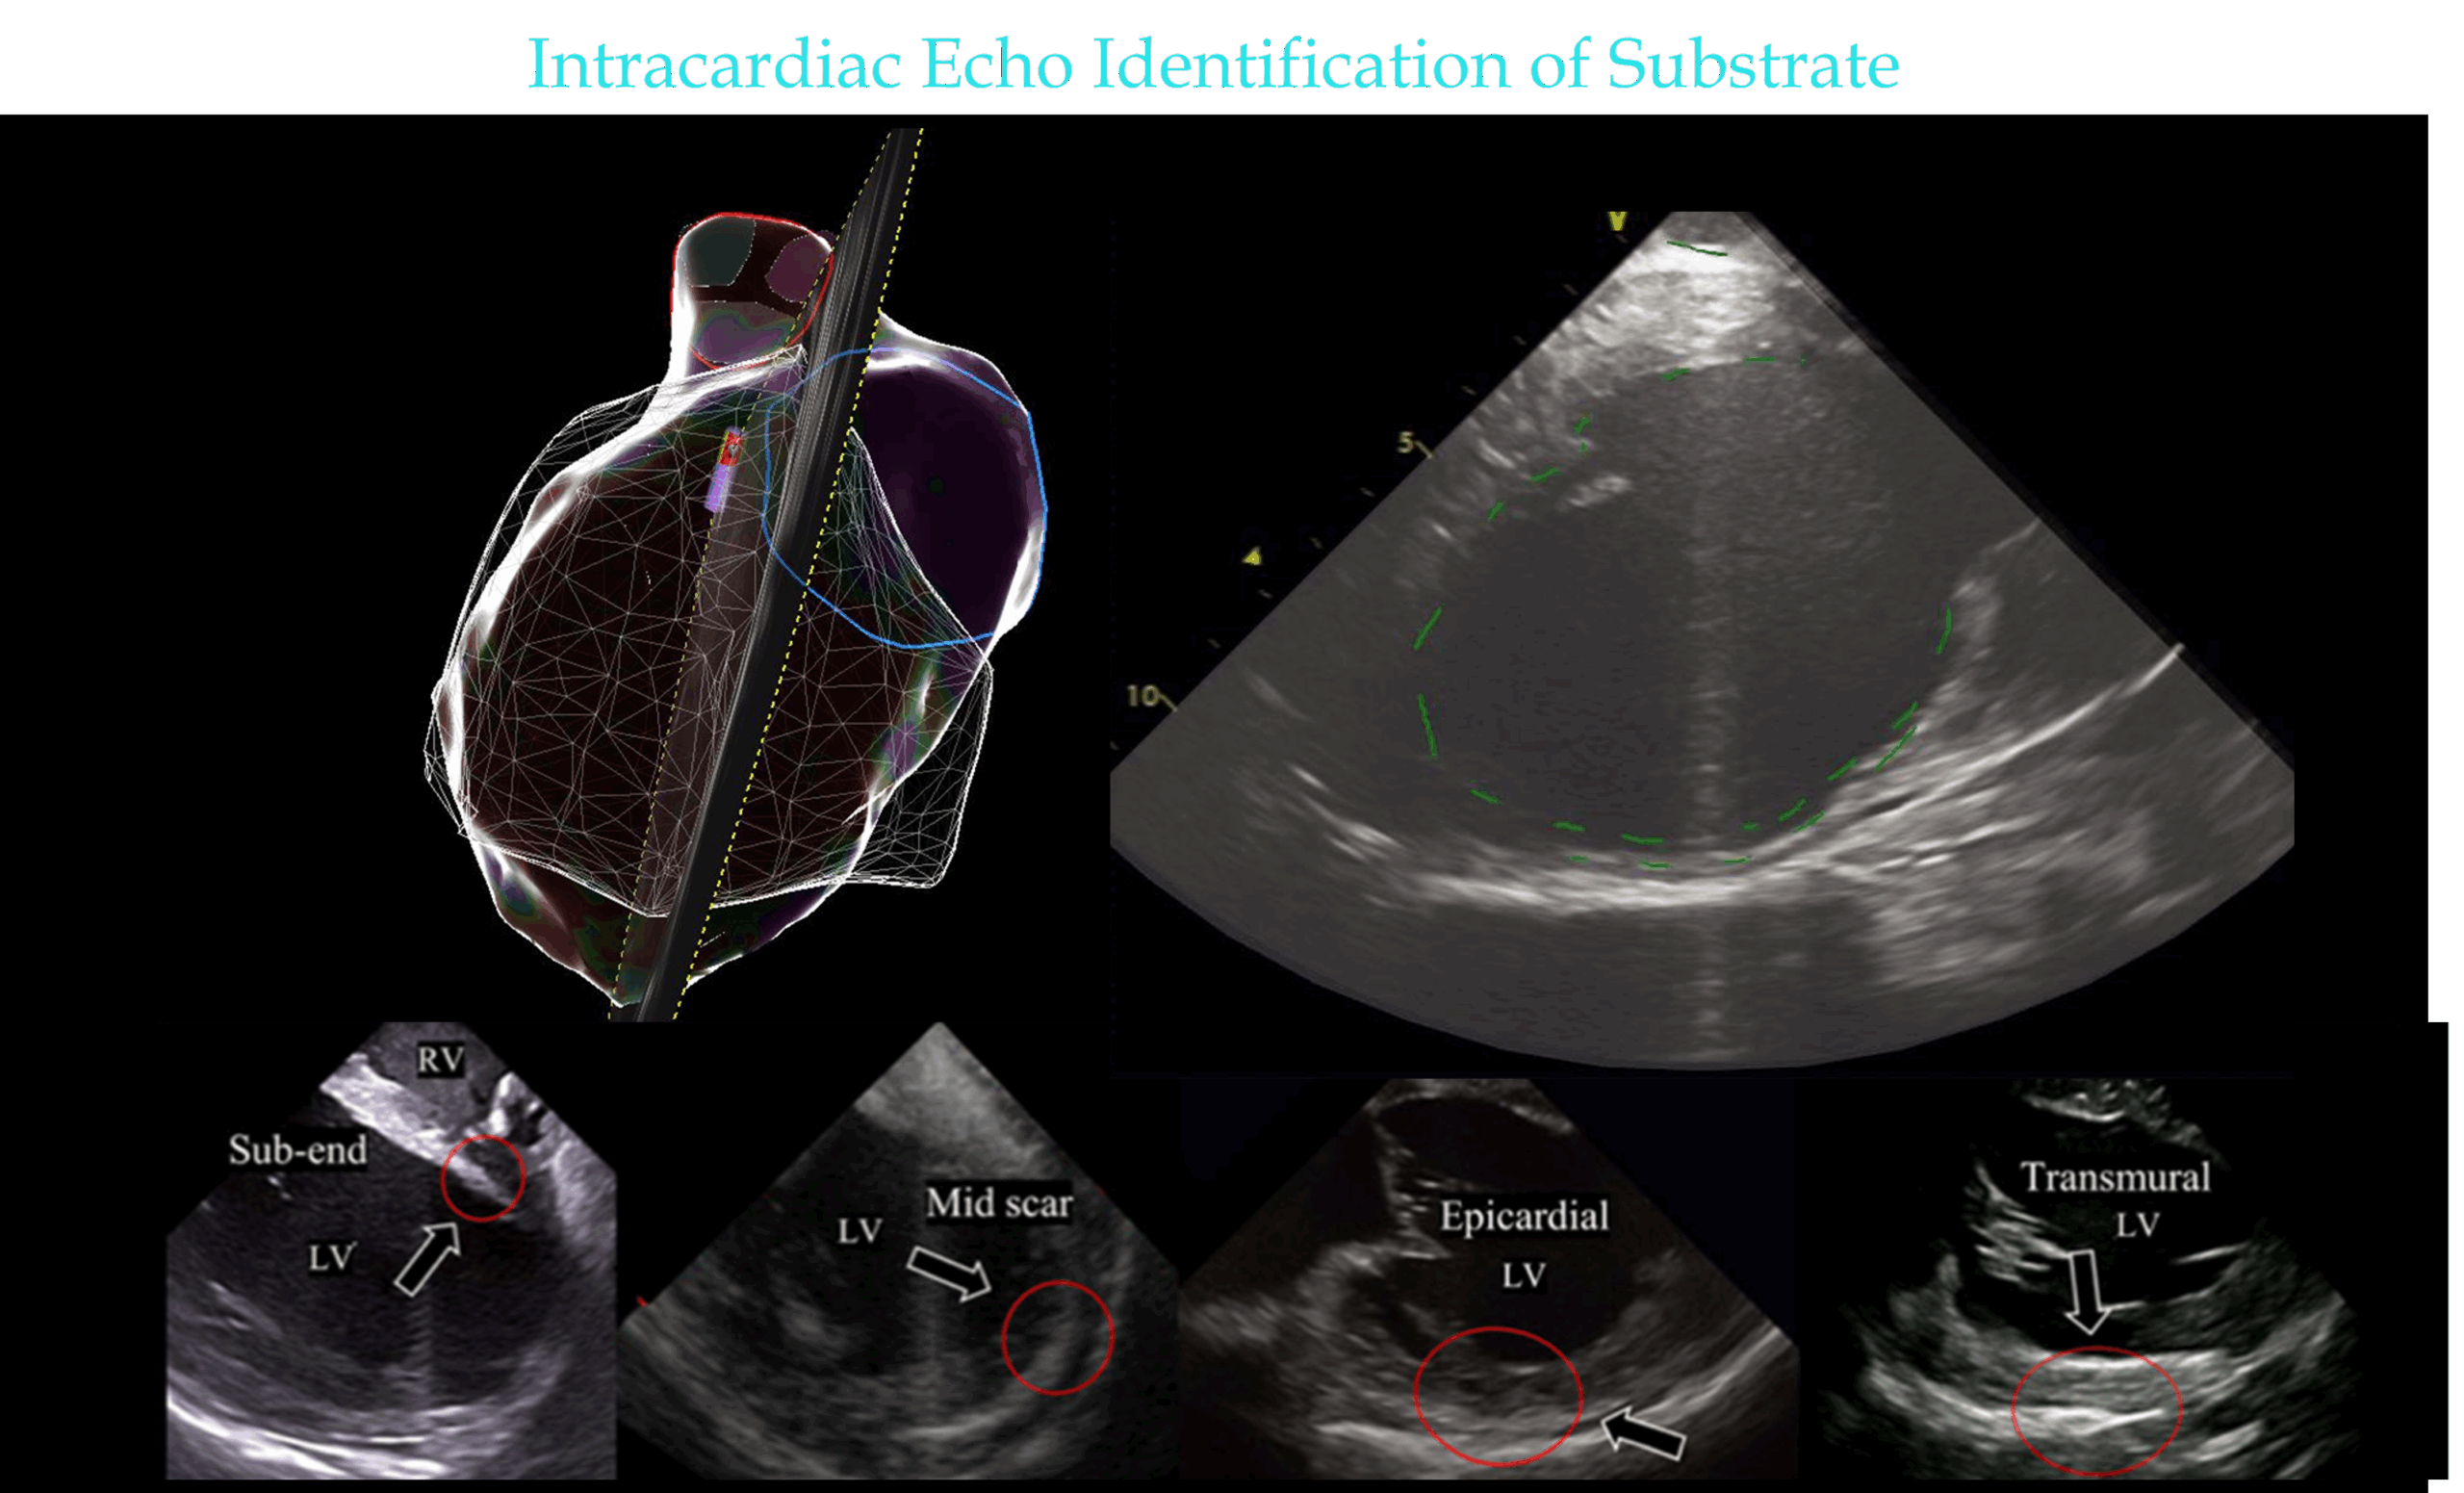

Intracardiac Echo

• Regions of high echogenicity on Intracardiac Echo can also identify regions of scar.

• ICE has the advantage of identifying intramural & epicardial scar as well as endocardial scar.

• On ICE, myocardium that is thinned, akinetic, or has abnormal echo density can be delineated as scar, and has good correlation to scar defined by Electroanatomical mapping. These regions can be targeted for ablation.

images modified from: Kanawati J, De Silva K, Bhaskaran A, Turnbull S, Zhou J, Kotake Y, Kumar S, Campbell T. Intracardiac echocardiography techniques to identify ventricular arrhythmia substrate. Heart Rhythm O2. 2022 Jun 17;3(5):602-612.